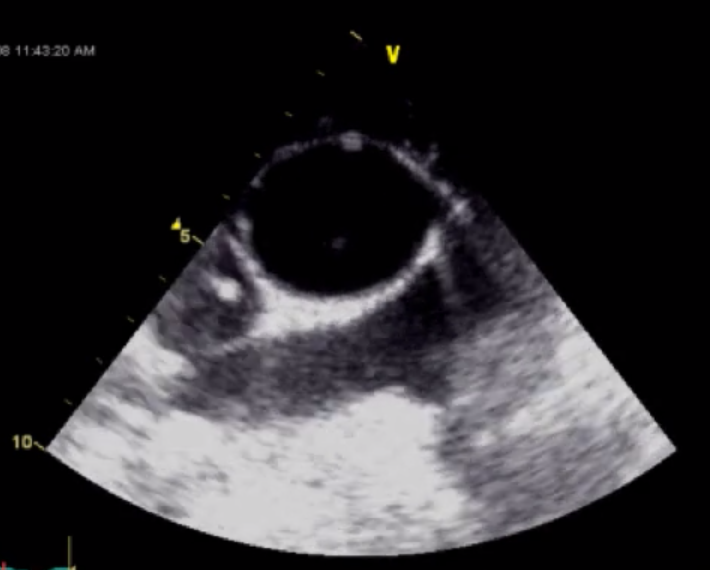

Label the following vessels

Big Circle = Mid Ascending Aorta

SVC = Small vessel on the right

Right PA at the bottom